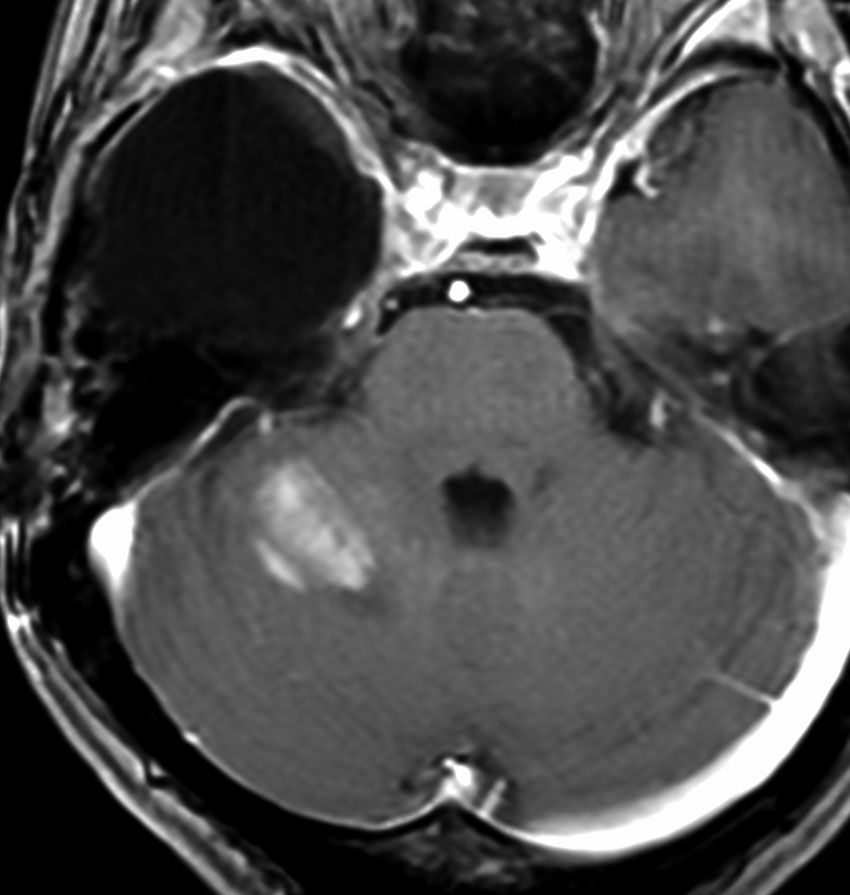

35歳,側頭葉てんかんで発症した右側頭葉の乏突起膠腫 グレード2です。全摘出して化学療法4コースと54グレイの局所放射線治療 generous local fieldを行いました。7年後に同じ部位に再発して摘出したところ退形成性乏突起膠腫 グレード3となっていました。手術摘出して,テモゾロマイド化学療法で維持療法をしていました。

その2年後の画像です。右小脳半球に再発しています。右側頭葉腫瘍との連続性は全くありませんでした。脳幹部にも腫瘍はありません。遠隔再発 remote recurrenceというもので,星細胞系腫瘍 astroytic tumor AAやGBMではよく知られている現象です。乏突起膠細胞系腫瘍でもまれにみられます。